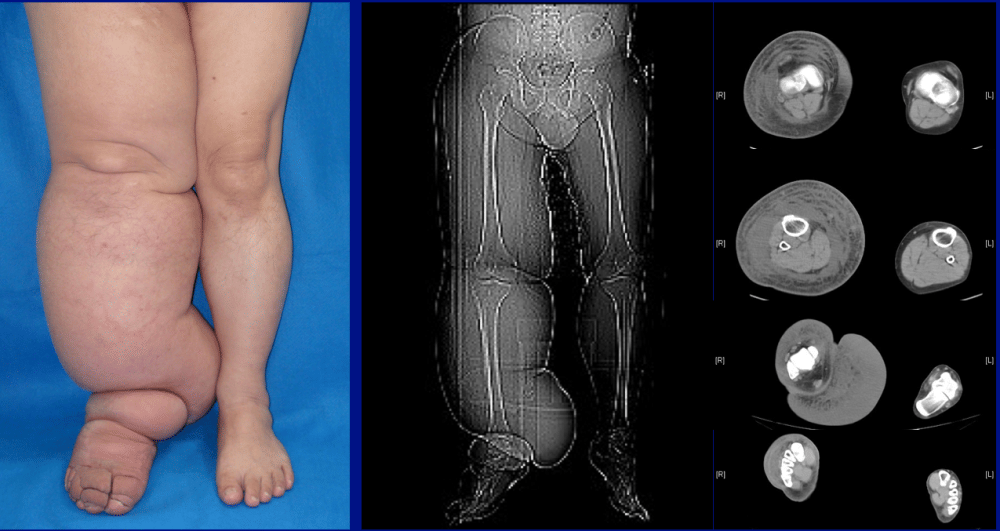

Tangerang, IDN Times - Selama bertahun-tahun, Engky (34) harus menderita dan menahan sakit lymphedema di kaki sebelah kiri. Tak hanya menderita, dia juga tak bisa bekerja dan beraktivitas karena kakinya membengkak hingga seberat 50 kilogram (kg).

Bahkan, dia juga sampai kesulitan melakukan aktivitas karena kakinya membesar sampai seberat 50 kilogram.

Ia mengungkap, kondisi pasien yang berat badannya sampai 230 kilogram ini, secara umumnya relatif stabil, baik itu tekanan darah, pernafasan dan sebagainya dengan kondisi normal.

Sementara itu, untuk keadaan penyakit lymphedema atau pembengkakan tungkai yang disebabkan oleh penyumbatan di pembuluh getah bening pada kaki kirinya itu masih dalam tahapan pemeriksaan tim dokter. Untuk pemeriksaan ini, pihaknya juga berkoordinasi dengan Rumah Sakit Cipto Mangunkusumo atau RSCM.